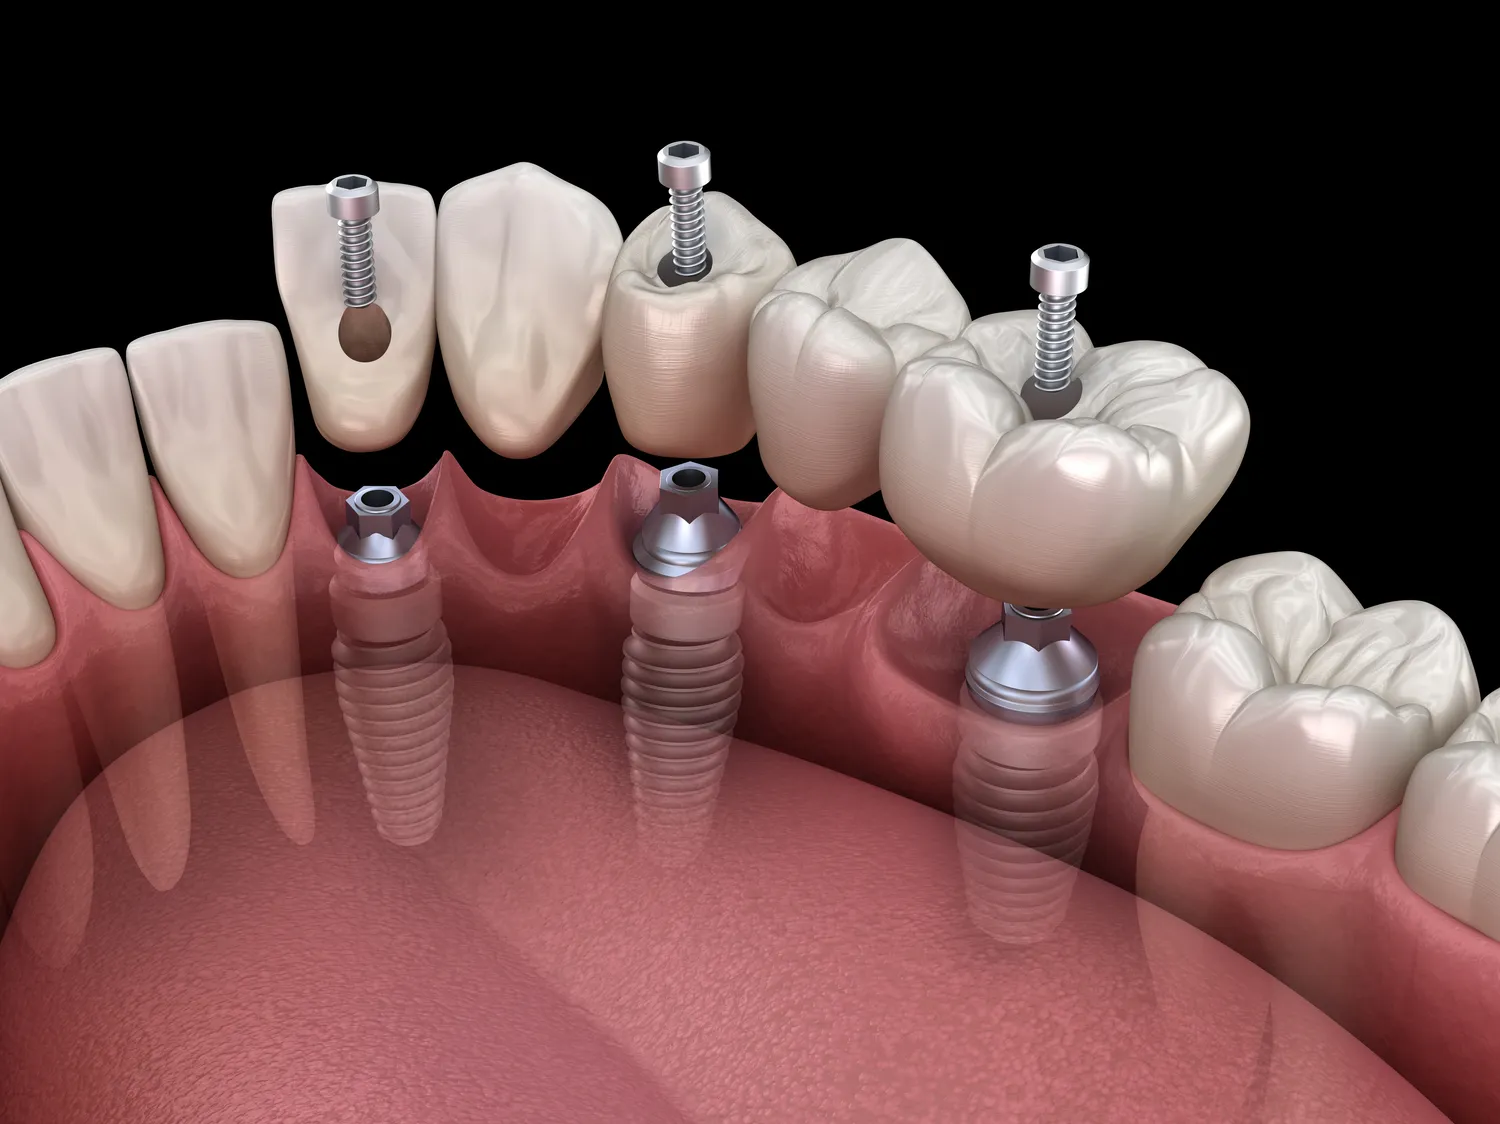

Wiele kobiet zastanawia się, jakie zabiegi stomatologiczne można wykonać w czasie ciąży bez obaw o zdrowie swoje i dziecka. Ogólnie rzecz biorąc, większość rutynowych procedur stomatologicznych jest bezpieczna, jednak zawsze warto skonsultować się z dentystą przed podjęciem decyzji o leczeniu. Profilaktyka jest kluczowa, dlatego regularne czyszczenie zębów oraz kontrole stanu zdrowia jamy ustnej powinny być priorytetem. W przypadku wystąpienia bólu zęba lub innych problemów zdrowotnych nie należy zwlekać z wizytą u dentysty. Leczenie kanałowe może być przeprowadzone w czasie ciąży, ale najlepiej jest to robić w drugim trymestrze. Ekstrakcje zębów również mogą być konieczne, a ich wykonanie powinno odbywać się pod odpowiednim znieczuleniem. Warto jednak unikać niektórych zabiegów estetycznych, takich jak wybielanie zębów czy zakładanie implantów, ponieważ mogą one wiązać się z ryzykiem dla rozwijającego się płodu.